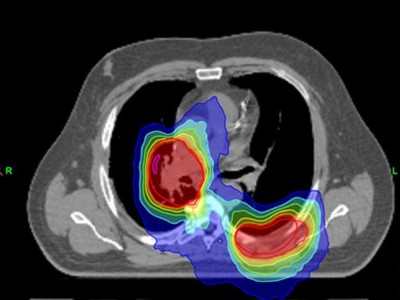

TKI und simultane thorakale Radiotherapie: ein vielversprechender Ansatz?

• NSCLC

• Kommentierte Studie

Die Ergebnisse einer aktuellen Studie liefern interessante Erkenntnisse zur Rolle einer kombinierten Tyrosinkinaseinhibitor(TKI)- und thorakalen Radiotherapie (TRT) bei oligoorganmetastasiertem, EGFR-mutiertem nichtkleinzelligem Lungenkarzinom (NSCLC). Jedoch sind einige Aspekte für die Bewertung der Arbeit zu berücksichtigen.

Kind erhält Leukämie Therapie/© FatCamera / Getty Images / iStock (Symbolbild mit Fotomodell), Immuncheckpointinhibitoren binden an Krebszelloberflächenproteine /© Juan Gärtner / stock.adobe.com, Arzt misst Blutzucker per Glucometer/© geargodz / Stock.adobe.com (Symbolbild mit Fotomodell), CT der Lunge mit Konsolidierungen (Pfeile) und Milchglastrübungen bei einer immunvermittelten Pneumonitis/© Minuth-Fuchs, K.L., Schulz, C. / all rights reserved Springer Medizin Verlag GmbH, Hepatozelluläres Karzinom im Lebersegment VIII/© Wengert, G. et al. / all rights reserved Springer Medizin Verlag GmbH, Blutabstrich der chonisch lymphatischen Leukämie/© jarun011 / Getty Images / iStock, Endobronchialer Befund mit exophytischem Tumor im Bereich des rechten Oberlappens/© Möller, M., Schütte, W. / all rights reserved Springer Medizin Verlag GmbH, Mann nimmt eine Tablette ein/© Jelena Stanojkovic / stock.adobe.com (Symbolbild mit Fotomodell), Thymom mit pleuraler Aussaat rechts im Masaoka-Koga-Stadium IVa./© Ried, M. et al. / all rights reserved Springer Medizin Verlag GmbH, Patientin schaut besorgt auf Infusionsbeutel/© KatarzynaBialasiewicz / Getty Images / iStock (Symbolbild mit Fotomodellen), Ältere Frau nimmt Tablette ein/© amenic181 / stock.adobe.com (Symbolbild mit Fotomodell), Generalisierte, konfluierende, kokardenartige Erytheme mit zentraler Blase/© Springer Medizin Verlag GmbH, Bronchialkarzinom/© Dr. Myriam Koch , Pulmonales Adenokarzinom bei Diagnosestellung/© Springer Medizin, Bestrahlung eines Lungenkarzinoms/© Springer Medizin Verlag GmbH, Search Icon, Ältere Frau fasst sich an die Brust/© Jelena Stanojkovic / Stock.adobe.com (Symbolbild mit Fotomodell), Person setzt DNS-Probe in Maschine ein/© Vit Kovalcik / stock.adobe.com, Mann raucht Joint/© Daniel Sierralta / Westend61 / stock.adobe.com (Symbolbild mit Fotomodell), Blut in Toilette/© stylefoto24 / stock.adobe.com